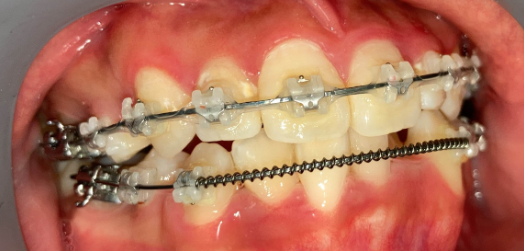

リカバリー症例1

他院の非抜歯矯正後、当院で再治療したケース

抜歯矯正1年後の口腔内|奈良の矯正歯科

治療1年後

他院で非抜歯矯正を受け、歯並びは改善したものの、口元の突出感が残ったまま治療が終了。当院で精密検査を行った結果、上下4本の抜歯によるリカバリー治療が必要と判断しました。